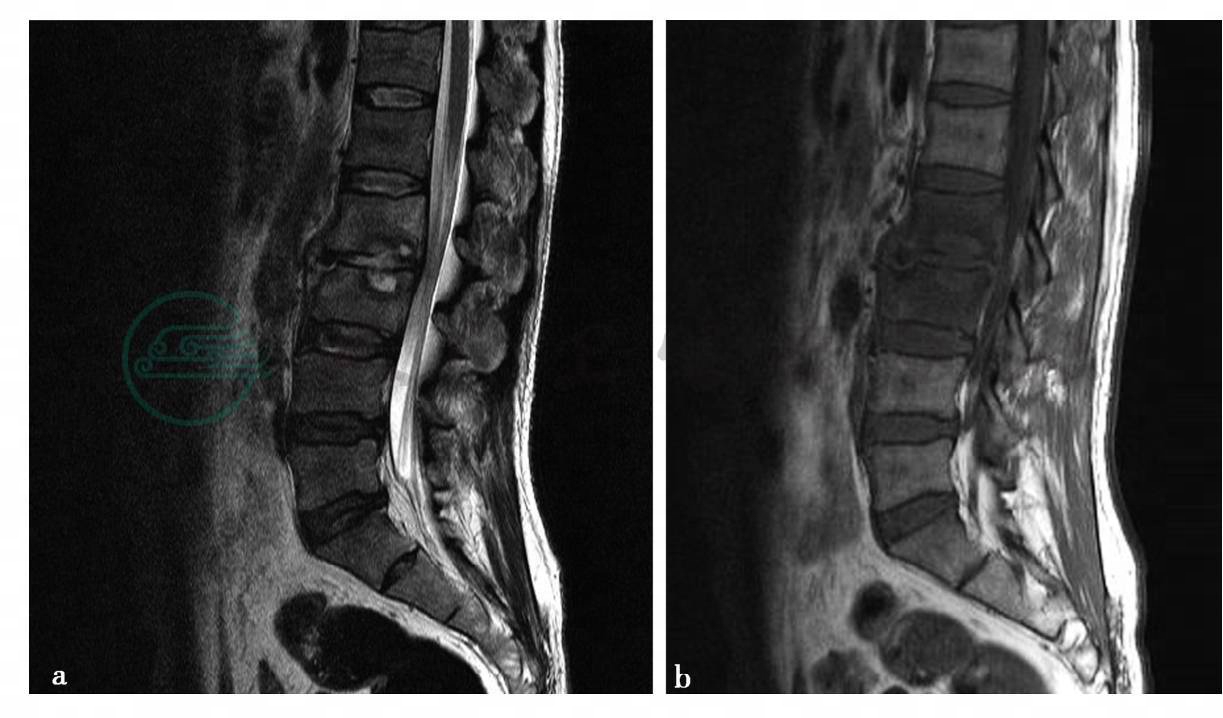

(1)病例1:

CT平扫及MRI平扫、增强扫描。

图1 a、c、d,CT平扫示矢状面重建图像显示腰椎生理曲度变直。L3椎体变扁,骨质破坏,呈碎片状改变,骨碎片向前后方向突出,导致骨性椎管变窄。L4椎体后上缘可见溶骨性骨质破坏,无硬化边。L3/4椎间隙变窄,L3椎体周围可见软组织肿胀,并波及左侧腰大肌。图17b,MRI示腰椎生理曲度变直。L3椎体显著变扁,骨质破坏,相应水平硬膜囊显著受压,在T2WI上脑脊液信号消失。L3/4椎间隙变窄。椎旁软组织肿胀,波及双侧腰大肌,形成脓肿,以左侧为主。图1e,L3/4椎体内可见片状T1WI低信号。图1f,T2WI呈等或低信号。图1g,STIR序列均呈高信号

(2)病例5-2-8:

图2 d、f、g,CT平扫示矢状面重建图像显示腰椎生理曲度略变直。L2、L3椎体内可见多发斑片状溶骨性骨质破坏,边缘清楚,周围无骨质硬化。L2/3椎间隙变窄,骨性椎管无变窄,椎旁软组织稍肿胀。图2a、b、c,MRI示腰椎生理曲度略变直。L2/3椎间隙变窄。L2、L3椎体相对缘骨性终板骨质破坏。图2b,T1WI呈低信号。图2a,T2WI呈稍高信号,信号不均匀图2c,STIR序列呈高信号。L2、L3椎体在T1WI(图b)上呈均匀低信号,在STIR(图d)上呈均匀高信号。椎旁软组织肿胀,多发小囊状信号影。硬膜囊略受压

(1)病例1,(腰3、4椎体)结核(边缘型)。

(2)病例2,(腰2、3椎体)结核(边缘型)。